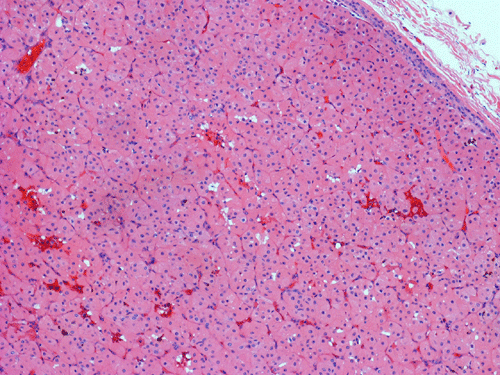

Pathology of the Case: Grossly, the tumor was a small 1 x 2 cm well demarcated nodule embedded within the mid portion of the salivary gland. There is no true capsule (Panel A). The tumor cells arrange in solid sheets and without specific pattern formation (Panel B and C). There is no collagenous tissue within the tumor. The tumor cells are polygonal and rather homogeneous in size. They have low-grade, centrally located nuclei (Panel D), finely granular and distinctly eosinophilic cytoplasm. The granular feature is best appreciated in the cytoplasmic preparation that is prepared while the tumor is being examined before fixation (Panel E). There is no necrosis or mitotic figures.

Microscopically, oncocytes have a very characteristic appearance with granular eosinophilic cytoplasm due to marked increase in the number of mitochondria mitochondria, pleomorphism of mitochondria, and a paucity of other organelles. The tumor cells have little variation among different tumors or different part of the same tumor. Characteristically, the tumor cells are rather uniform and polygonal in shape. The cytoplasmic membrane can be readily recognized. The nuclei are usually round, centrally located, and nucleoli are present. The cells are arranged in uniform solid sheets without a specific pattern or they may aggregate into clusters, and sometimes they form duct-like structures. Thin fibrovascular septa are present. Oncocytomas may have a clear cell component secondary to accumulation of cytoplasmic glycogen 6. A PAS stain with and without diastase digestion will be very helpful in recognizing the glycogen. High grade nuclear atypia is only seen exceptionally. Phosphotungstic acid hematoxylin (PTAH) is a good stain that would stain the mitochondria dark. However, the stain is rarely called to service for this purpose as the cytoplasm is typically characteristic enough for recognition without special stain. In clear cell variants, however, PTAH may help. Mitotic figures are not readily seen. In most situations, the diagnosis of oncocytoma is not a particularly challenging one.